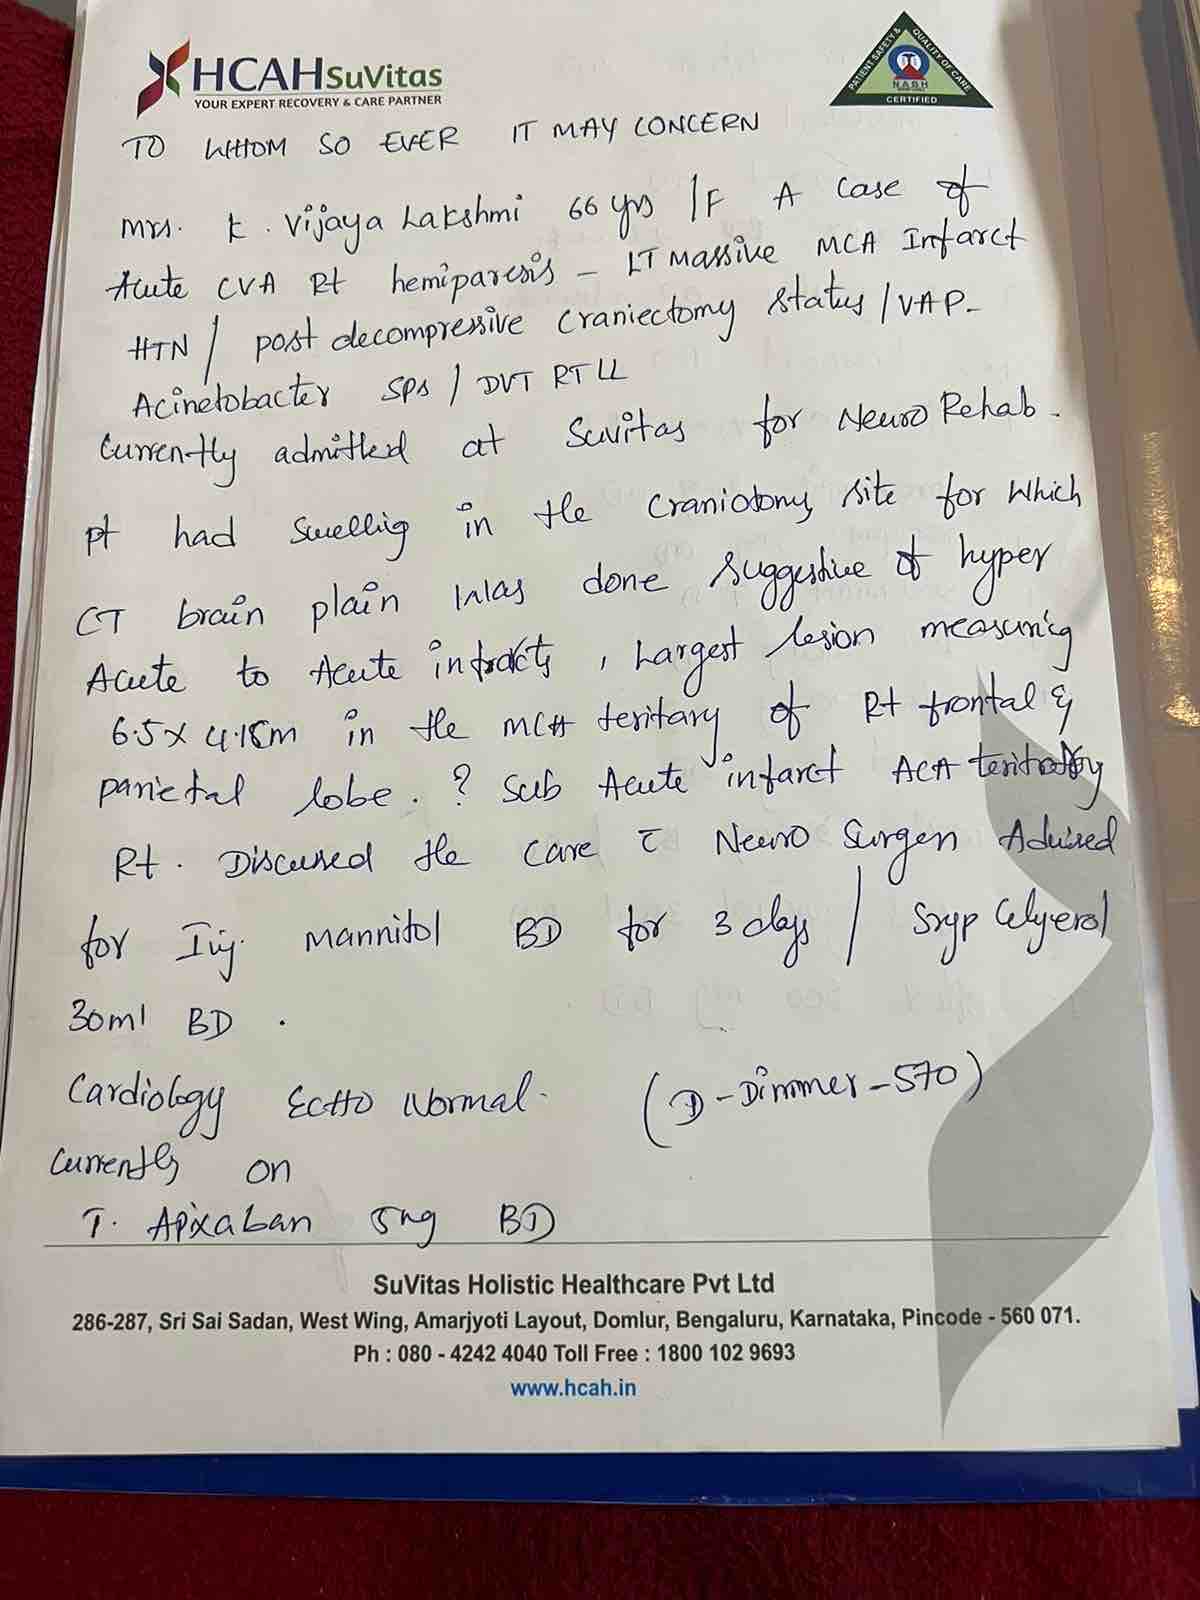

We are reaching out to you today with a heavy heart and a plea for help. Our beloved 66-year-old mother K VIJYA LAKSHMI, has been facing an incredibly challenging journey since 16th May when she had brain stroke & underwent emergency brain and abdomen surgery. Her recovery has been a rollercoaster of ups and downs.

During her hospitalization, she endured multiple complications, including respiratory distress, recurrent severe infections, and even seizure-like activity. Through it all, she has shown immense strength and determination. Still she require three more surgeries to stand on the path of recovery.